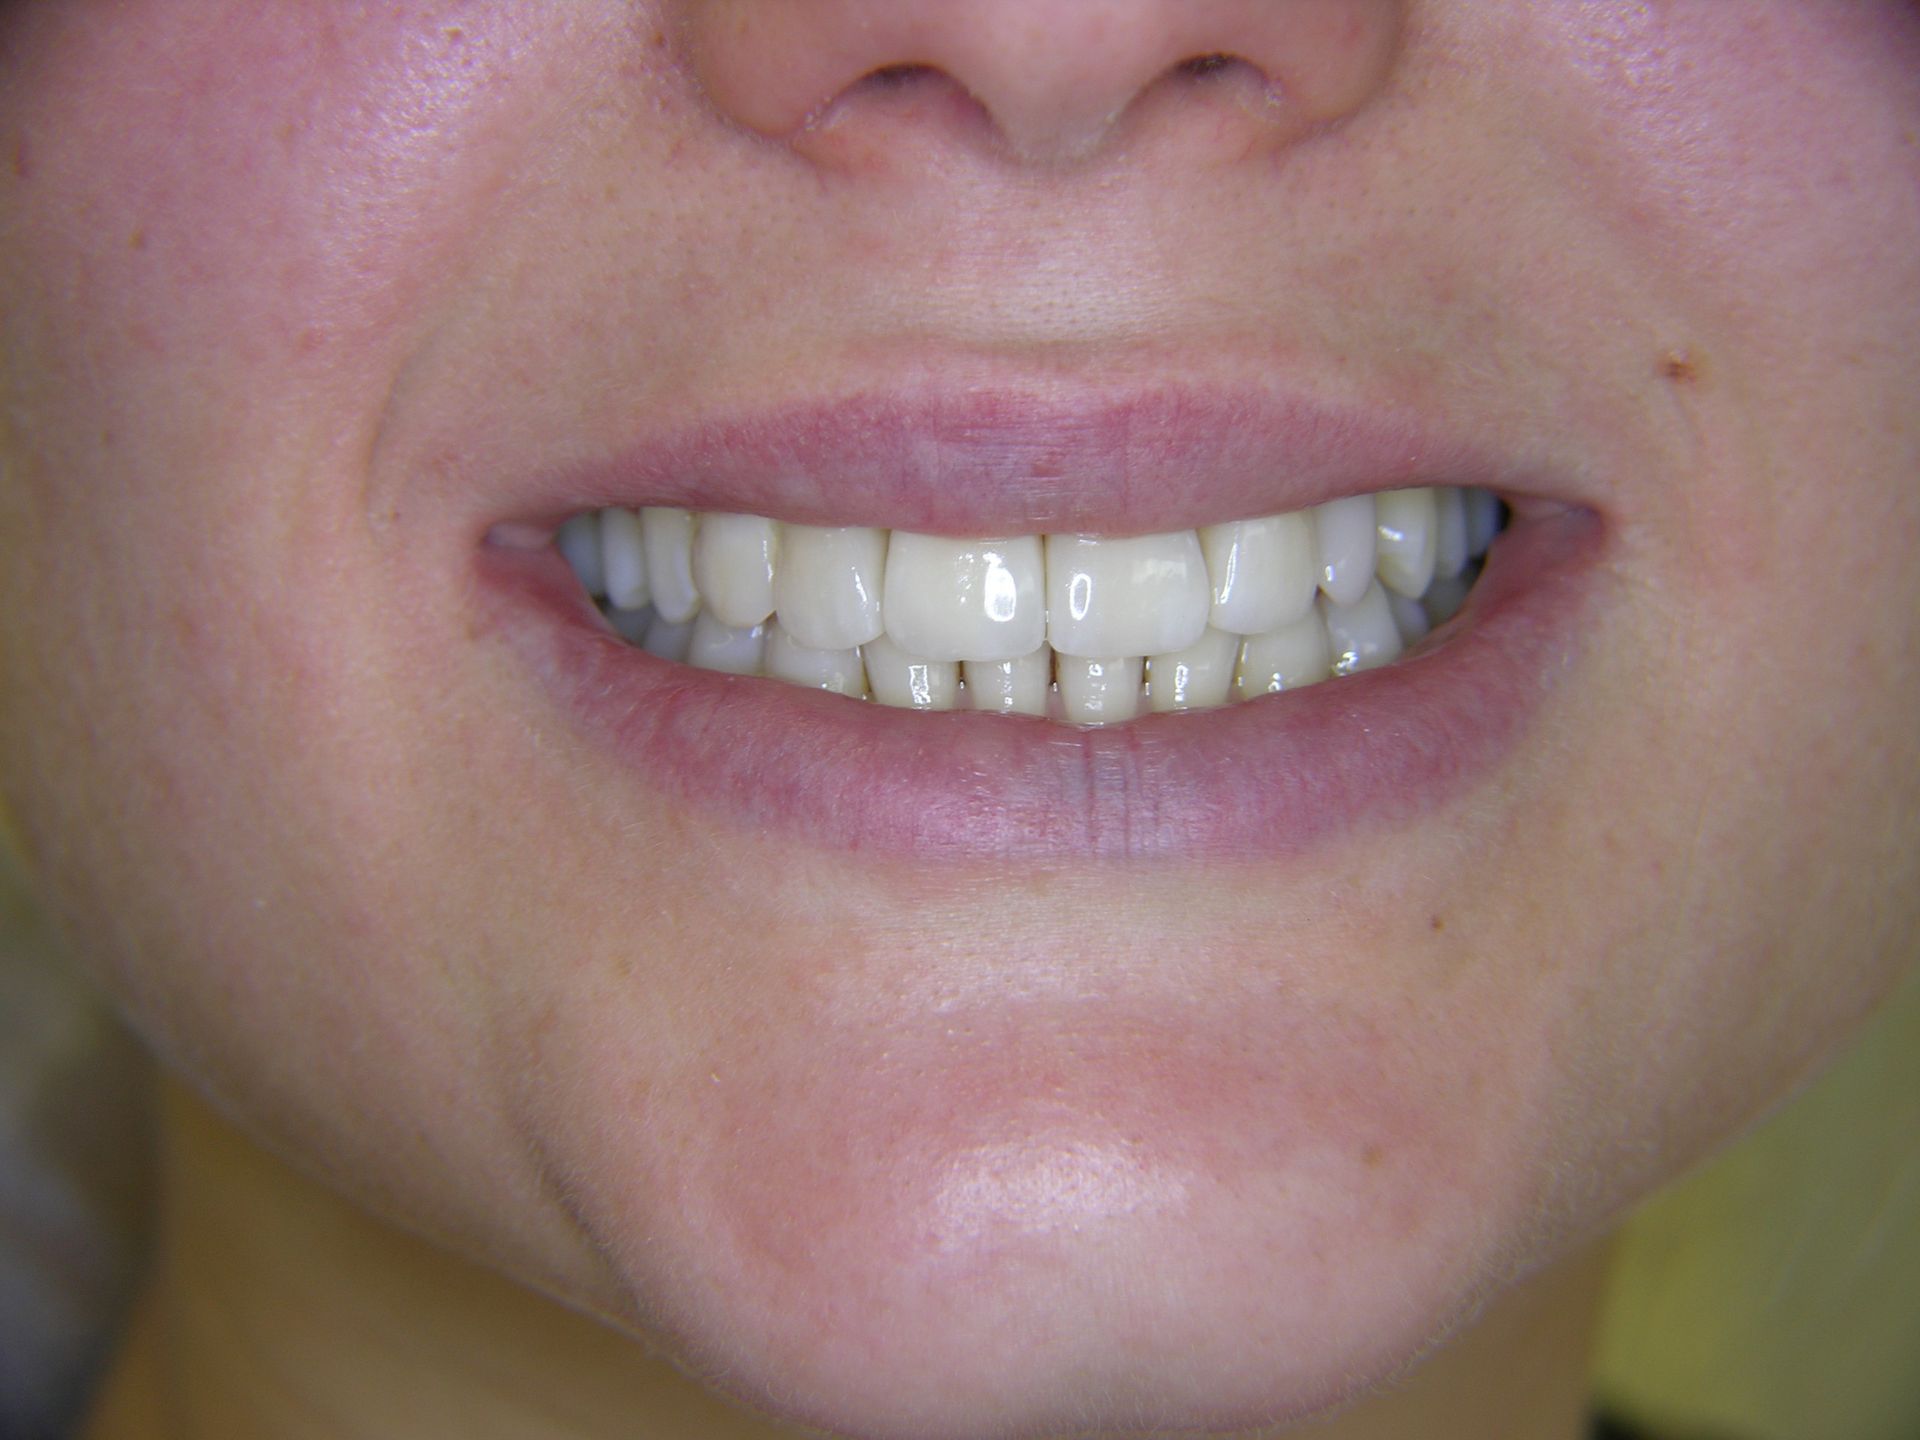

Beispiele von Versorgungen